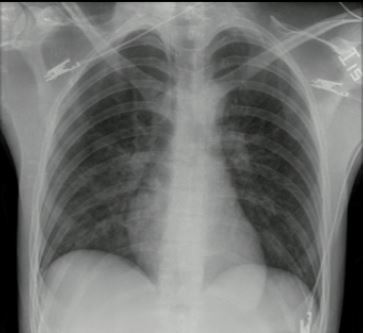

Se le tomaron exámenes paraclínicos, entre ellos radiografía de tórax, que reveló opacidades mixtas de predominio alveolar en ambos campos pulmonares, con tubo endotraqueal a 4 cm de la carina ( figura 2). También gases arteriales después del inicio de la VMI con un pH de 7,26; PO 2 de 70 mm Hg; PCO 2 de 35 mm Hg; HCO 3 de 15 BE-15; SO 2 al 80%; hemograma con leucocitos de 7600; hemoglobina de 18 g/dl; hematocrito al 54%; neutrófilos al 78%; plaquetas: 301.000; creatinina: 2,61 mg/dl. Electrolitos: sodio de 135 mmol/l; potasio de 5,3 mmol/l; cloro de 104 mmol/l.

Se le continuó el manejo al paciente en la unidad de cuidados intensivos durante, aproximadamente, 9 días más. Posterior a esto, salió al servicio de hospitalización sin dificultad respiratoria y sin requerimiento de oxígeno domiciliario ( figura 3). Luego, el manejo estuvo a cargo del grupo de psiquiatría, al cual el paciente le comentó que desde la adolescencia había consumido múltiples sustancias psicoactivas. Se encontraron rasgos mal adaptativos de la personalidad. Durante un día más estuvo hospitalizado, sin síntomas de abstinencia y en fase contemplativa de ingreso a un programa de rehabilitación, al que actualmente se encuentra asistiendo.